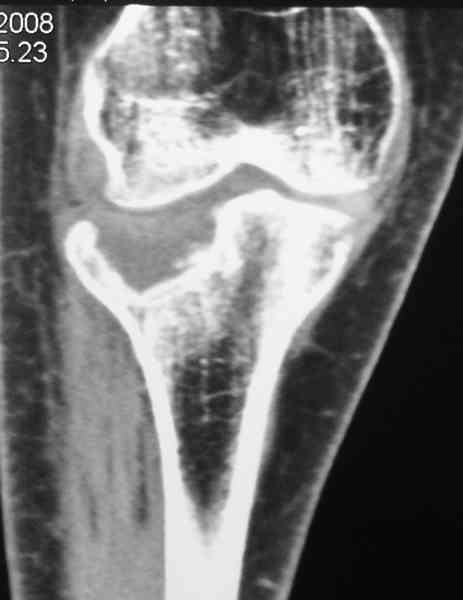

Есть ли возможность сделать КТ?

К большому сожалению КТ пока на ремонте, как запустять, сразу сделаю. Спасибо.

Я согласен с мнением доктора Соломина, что необходимо выполнить СТ. Это поможет Вам не только определить степень повреждения твёрдых тканей, но и увадеть степень сращения. Без СТ не возможно планировать дальнейшую тактику лечения.

У пациента основной проблемой является импрессионый перелом наружного мыщелка, уже неправильно сросшийся, по-видимому. Аппаратом закрыто можно только подправить угол на уровне метадиафиза. Что

улучшит разве что внешний вид конечности, но не решит основной проблемы - грубой деформации суставной поверхности.